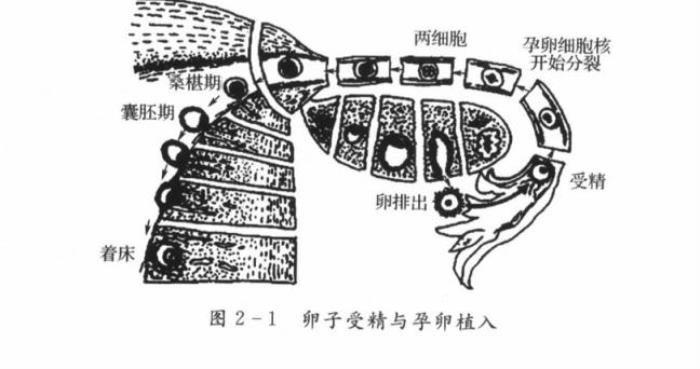

前面其实提到过一种情况,那是在孕早期,医生通过阴超检查可以清晰地查探清楚受孕胚胎在孕妈们腹中的发育情况。

在准妈妈受精(精子与卵子结合的过程)后,受精卵会在子宫内着床,也就是这时受精卵发育成囊胚侵入到子宫内膜并埋于其中。着床成功后,囊胚与子宫内膜将同步发育并相互配合。

受精卵着床示意图。图源:邦彦医院学习资料

当孕妇接受阴超检查时,检查探头距离胚胎还是有一段距离的,虽然探头会轻轻触碰到子宫边界,但整个过程并不会损伤子宫,更不会引起出血等一系列不良情况。

实际上在孕妇的日常活动中,子宫也不是处于静止的状态,也会产生一些晃动,有些晃动幅度甚至比探头的触碰还大,但其中的胚胎依旧安然无恙。

所以担心阴超探头会伤害到宝宝,实在是无稽之谈。